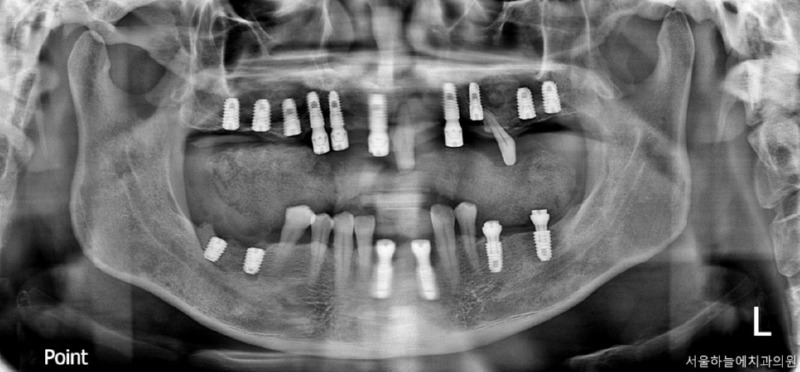

당뇨·고혈압을 모두 가지고 계셨던

전악 임플란트 케이스

이번에 소개해드릴 환자분은

당뇨와 고혈압, 두 가지 전신질환을

모두 가지고 계셨던 분으로

치아 결손이 광범위해

전악 임플란트가 필요한 상황이었습니다.

· 상악은 잇몸뼈가 매우 얇고 치아가 거의 남아 있지 않은 상태

· 하악은 부분 결손과 앞니의 심한 동요

· 식사가 어려울 정도로 기능 저하가 심한 상태

치료 계획 및 수술 과정

이 환자분은 다음과 같은 계획으로

치료를 진행했습니다.

· 수면마취(의식하 진정요법) 하에 진행

· 상악 양측 상악동 거상술 + 임플란트 10개 식립

· 하악 발치 후 결손 부위 포함 임플란트 6개 식립